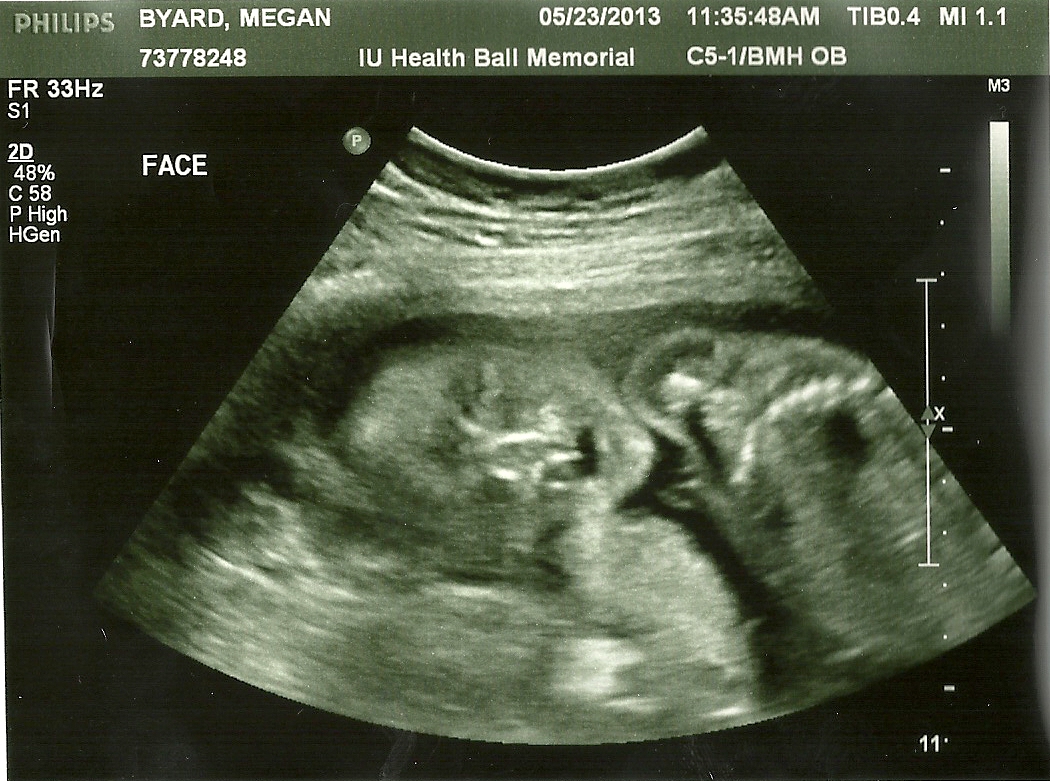

Ultrasound pictures:

At almost 23 weeks, she has a face!

Looks like she might sleep with her mouth open?  Well, we both do that, so she'll fit right in!

We have so much to do before she comes, but I'm so ready to meet her!  The ultrasound tech said she was perfect in every way; everything is working and she has all the parts she needs (they checked about a million things like kidneys, sections of the brain, the heart, the spine, the eyes...EVERYTHING).  Also she is very photogenic--every time the tech told us she was going to begin looking for the next item, baby would literally spin and offer that part of her body up for pictures.  What a turkey!  The only concern right now is that she's breech, but she's got about 10 weeks to turn herself around before the doctors begin to worry that she won't do it herself.  I say she can take her time as long as it gets done, but hopefully she won't procrastinate about it!